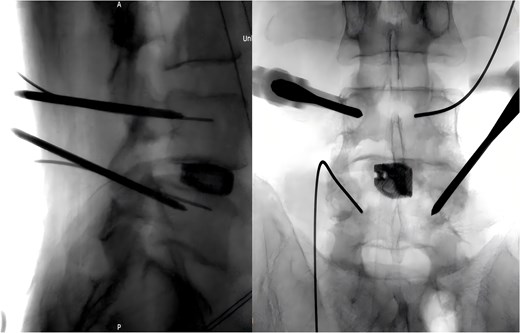

Following removal of the left L5 pedicle screw during the procedure, the smallest endoscopic sheath was inserted along with the endoscope to explore the screw trajectory. Under fluoroscopic guidance, endoscopic forcep was utilized to identify and grasp the fractured guidewire (Fig. 4). Tactile feedback of a metallic sensation confirmed precise localization. Approximately 6 mm of the fractured guidewire was successfully extracted (Fig. 5). Subsequent fluoroscopy confirmed complete removal of the broken guidewire. The left L5 pedicle screw was reinserted, and bilateral connecting rods were placed. The nuts were then securely fastened. Hemostasis was confirmed under endoscopic visualization, and the surgical incisions were closed and dressed with sterile coverings.

Following the surgery, the patient remained in stable condition with no reported discomfort. Postoperative radiographs verified complete extraction of the guidewire, with no residual fragments observed at the fracture site (Fig. 6). The patient experienced an uneventful recovery, and subsequent follow-up evaluations demonstrated satisfactory outcomes.

Postoperative anteroposterior and lateral radiographs of the lumbar spine.